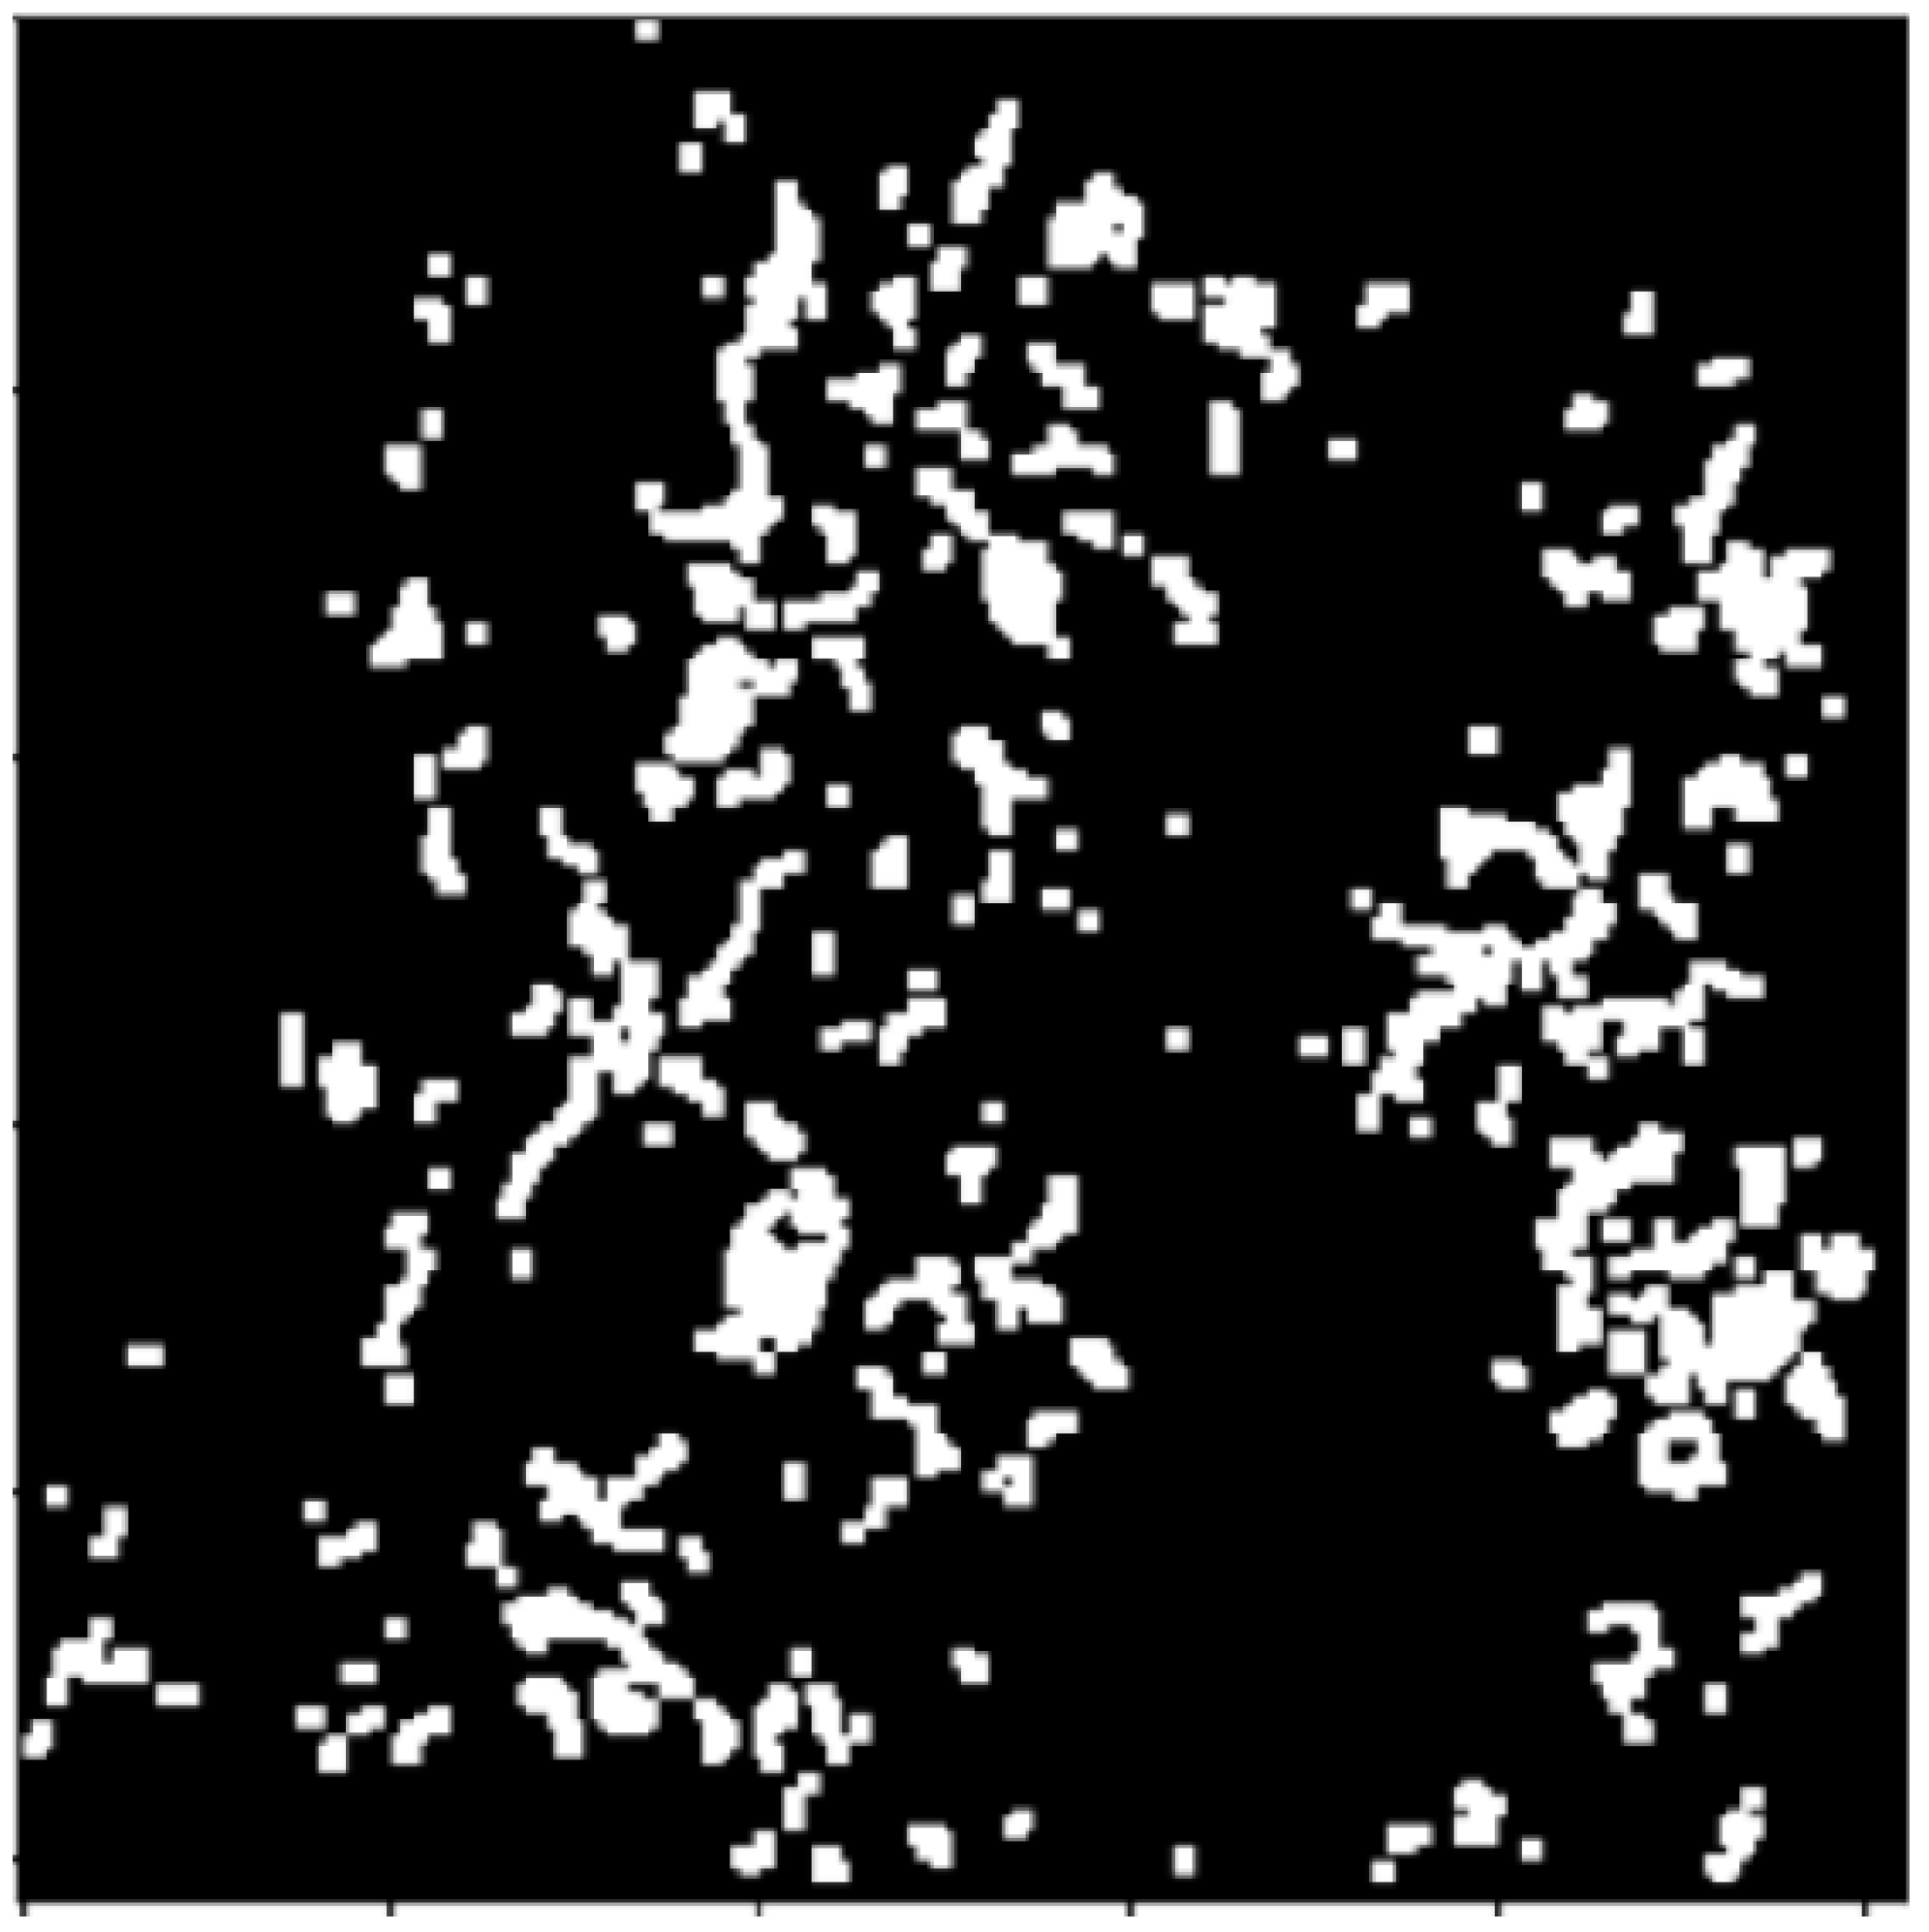

2.2.2. Morphology Operations

2.3.1. Connected Components